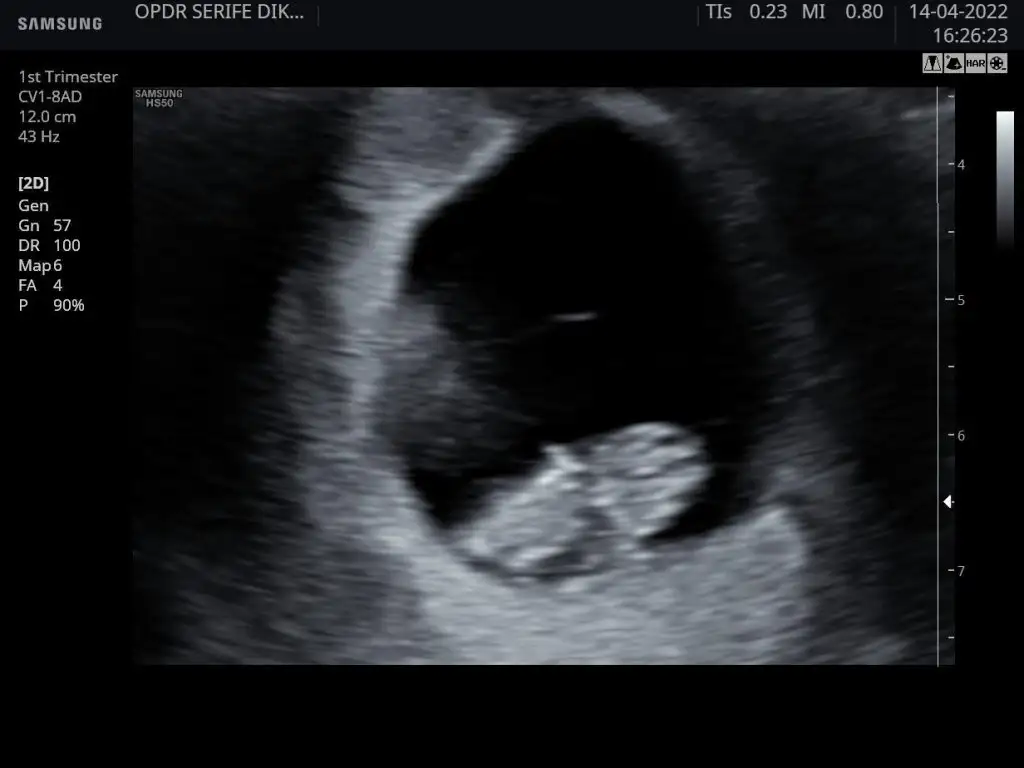

Tam 9. Haftada karından ultrason görüntüsü. Cinsiyeti ne olabilir, ben de merak ettim😊 Pasha22 Pasha22